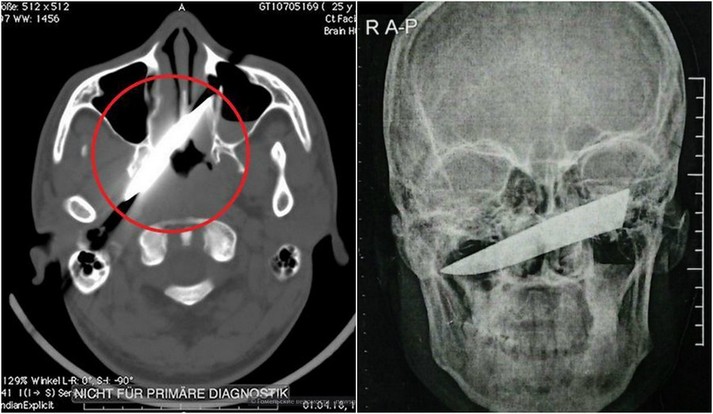

Рентген показав, що ніж зайшов на 10 см в голову, але не зачепив жодної артерії

Удар ножем в око він отримав під час п'яної бійки в барі. Після цього потерпілий як ні в чому не бувало відправився додому спати. Наступного дня чоловікові все ж довелося відвідати медичний заклад. Леза він не помітив, однак голова і очі дуже боліли. Рентген показав, що ніж зайшов на 10 см в голову, але не зачепив жодної артерії. Лікарі навіть вирішили перенести операцію на чотири дні, поки оформлялися необхідні документи.